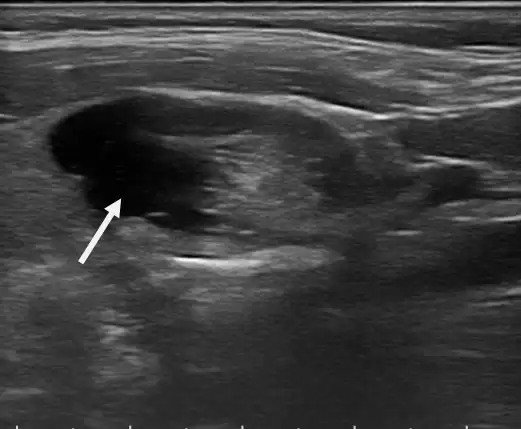

今年春天,在朋友推荐下,张阿姨找到了西湖大学医学院附属杭州市第一人民医院超声影像科副主任医师徐陈柯。超声检查很快给出结果:一枚约3.5×1.7×2.3cm的甲状腺囊实混合性结节,因为位置靠前,所以让外观有了明显变化。

术前超声检查出来的甲状腺囊实混合性结节